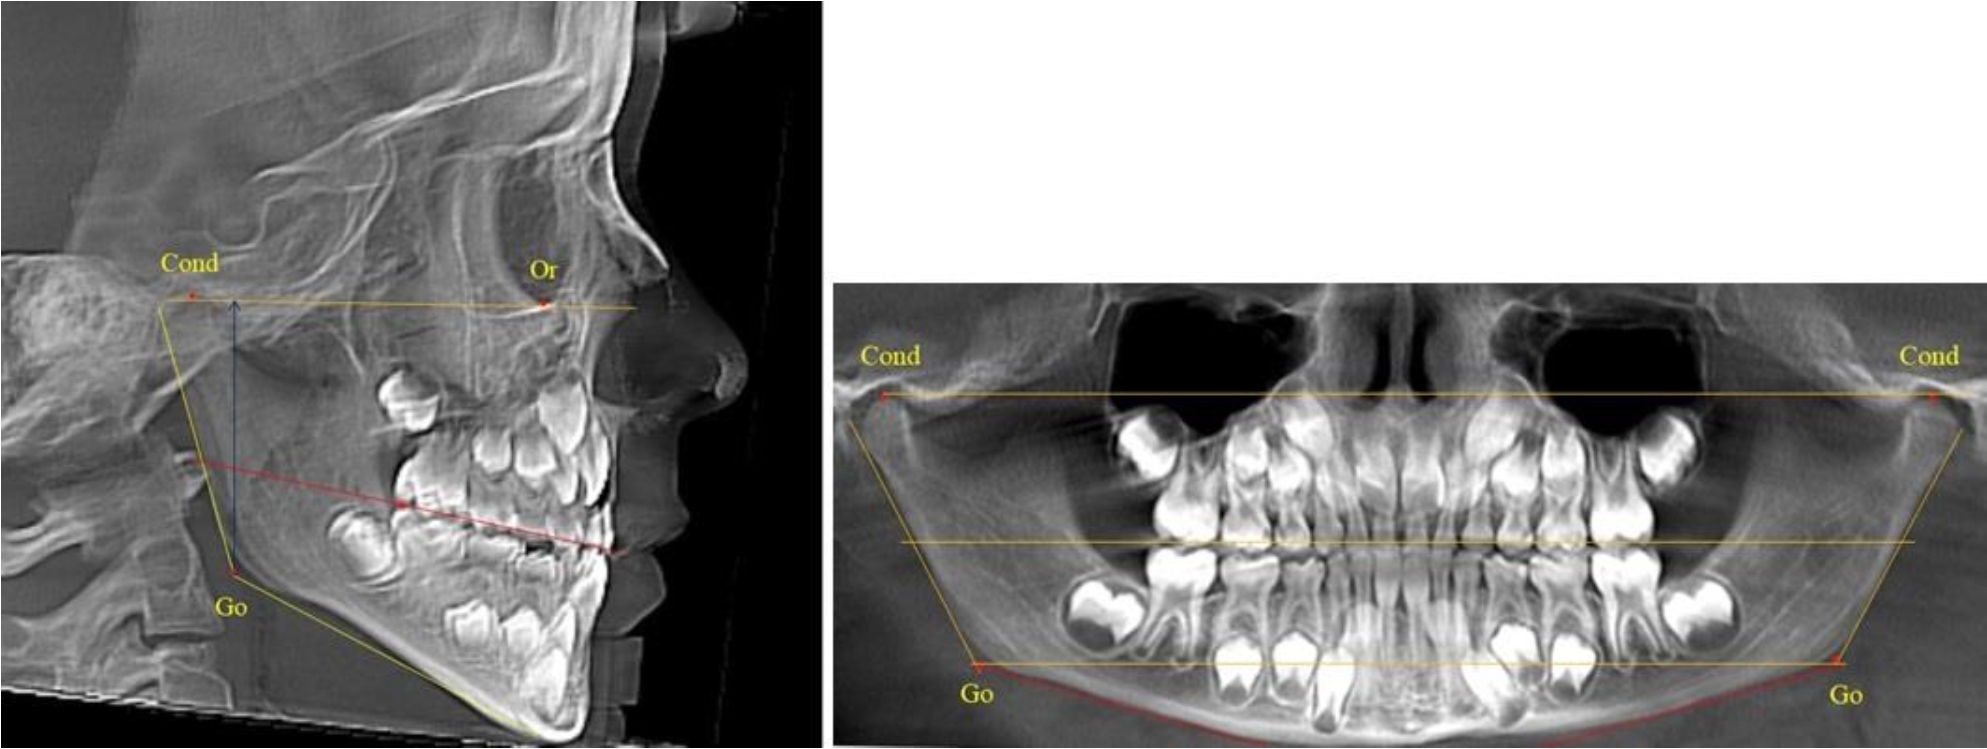

На всех парах рентгенограмм угол нижней челюсти, измеренный на телерентгенограмме, так же, как и в 1-й группе, соответствовал углу, полученному при построении угла на ортопантомограмме. Окклюзионная линия делила ветвь на два отдела (рис. 2).

Рис. 2. ТРГ и ОПТГ пациента после прорезывания первых постоянных моляров

Как на ортопантомограмме, так и на телерентгенограмме высота ветви у детей 2-й группы составляла (46,54 ± 2,87) мм, что было несколько больше, чем у детей 1-й группы (р ˂ 0,05). При этом высота верхней окклюзионно-суставной части была (25,42 ± 1,59) мм, а нижней – (21,12 ± 1,77) мм.

Таким образом, верхняя часть была несколько больше нижней, что и определяло рост обеих частей ветви.

Относительные показатели соразмерности частей ветви нижней челюсти показали, что отношение высоты верхней части ветви к нижней в среднем составляло 1,21 ± 0,12. Отношение общей высоты ветви к верхней ее части составляло 1,83 ± 0,13, а отношение общей высоты ветви к нижней ее части было 2,20 ± 0,16, и достоверных различий по относительному показателю отношения всей высоты к верхней и нижней челюсти нами не отмечено (р ˃ 0,05).